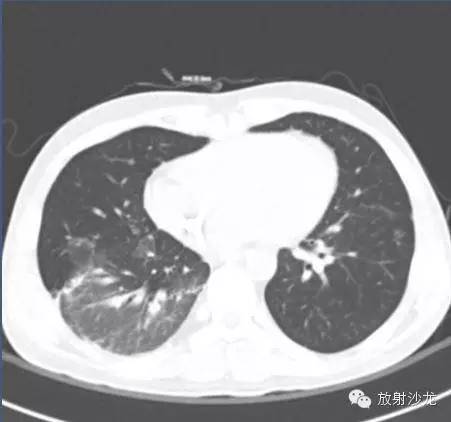

(第一次胸片示两肺中野及右肺下野多发斑片状高密度影。胸部CT示多发斑片状磨玻璃样密度增高影以及实变影,同时伴有小叶间隔的增厚。其中有些病灶部分表现为“铺路石征”。两周后CT随访显示这些病灶的密度和范围都增大。电视辅助胸腔镜肺活检下,活检标本病理诊断结果为急性纤维素性机化性肺炎。上述病变经高剂量糖皮质激素治疗三周后明显改善。)

通过对急性纤维素性机化性肺炎患者发病年龄进行调查, 显示急性纤维素性机化性肺炎的发病年龄跨度较大,婴儿、老年人均可能患有急性纤维素性机化性肺炎。急性纤维素性机化性肺炎的临床表现主要为呼吸困难、胸闷、气短等呼吸系统症状, 很多患者起病较急。在急性纤维素性机化性肺炎的临床治疗过程中, 由于部分患者对类固醇及免疫抑制剂反应良好, 至今尚未形成统一的临床治疗方案。对于急性患者而言, 其会很快发展成为呼吸衰竭, 具有较高的病死率, 因而需要对这类患者进行机械通气治疗, 对于亚急性患者,其病程较长。